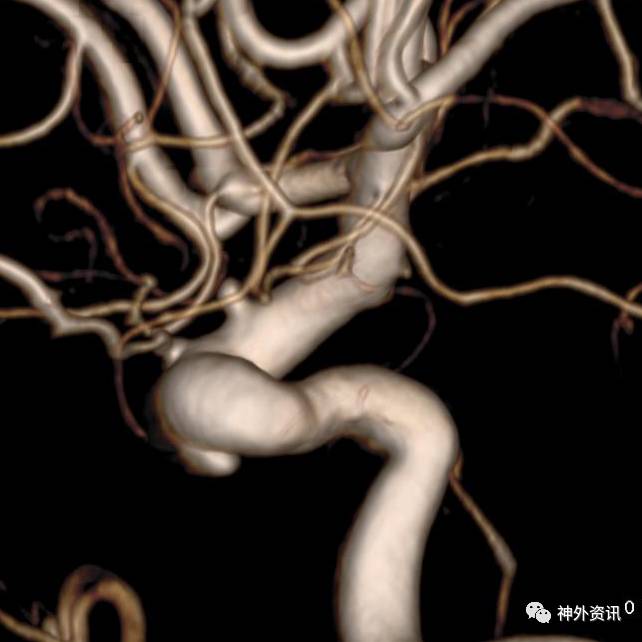

大C塑形

10mm以上的大动脉瘤:

(1)C型头端完全进入动脉瘤囊内,微导管的盘旋有利于均匀填塞

(2)避免微导管头端过早踢出

病例一